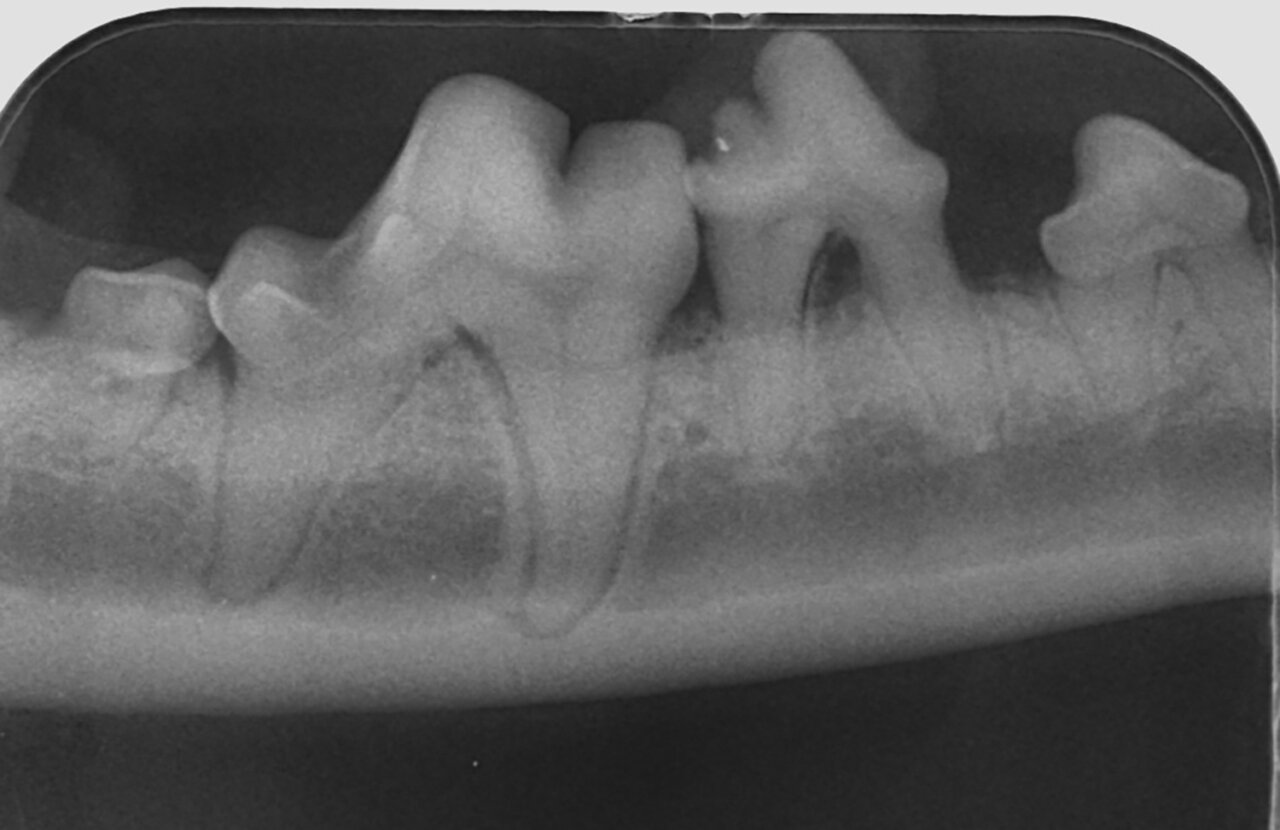

Además de permitirnos evaluar el grado de enfermedad periodontal, también hace posible seleccionar el mejor tratamiento en función de su patología y las posibles complicaciones, como las fracturas mandibulares iatrogénicas en perros de talla pequeña con enfermedad periodontal PD4 (imágenes 10 y 11).

Fracturas dentales

Las radiografías son esenciales en la detección y evaluación de las fracturas del hueso (alveolar, maxilar y mandibular) y del diente (tanto a nivel de la corona, para ver su relación con la pulpa, como de la raíz dental). Los dientes rotos o fracturados son un problema muy común en la práctica veterinaria.

El tratamiento, a menudo, depende de qué partes del diente estén afectadas, raíz y/o corona, y en el caso de esta última, de qué capa(s): esmalte, dentina y si hay exposición o no de la pulpa:

- Las fracturas que exponen el canal radicular se denominan fracturas complicadas y estos dientes con exposición directa de la pulpa deben tratarse mediante endodoncia o extracción (imágenes 21 y 22).

Cuando la fractura afecte a la raíz del diente este debe ser extraído (imagen 23).